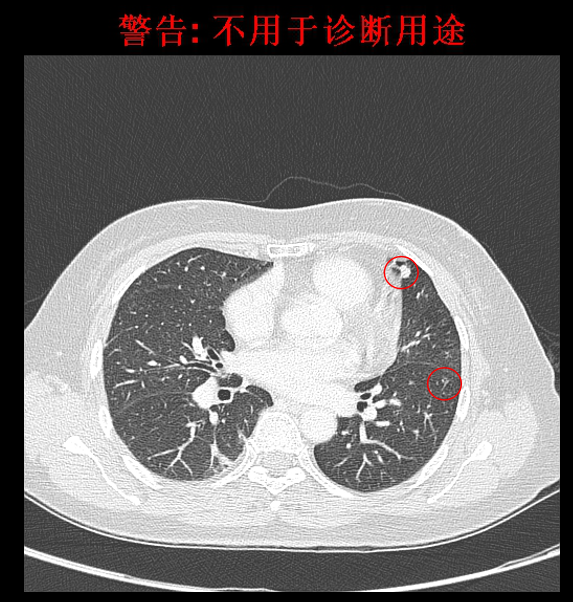

2016-4影像